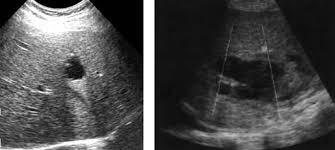

Ecografía abdominal en urgencias, sugiere masa que depende de cabeza de páncreas versus masa lobulada en zona del hígado, no líquido libre.

La paciente es ingresada en planta de medicina interna para estudio  donde se detecta por TAC (Tomografía Axial Computarizada) abdominal una lesión de 11.7 x 7.5 x 11 centrada en nasogastrío-hipocondrio derecho con componente intrahepático en segmento IV. Analítica anodina salvo alfa-fetoproteína elevada. Marcadores de virus hepatotropos negativos.

Se realiza Biopsia de aguja con aspiración gruesa  de la lesión guiada por ecografía con diagnóstico de carcinoma neuroendocrino de célula pequeña.